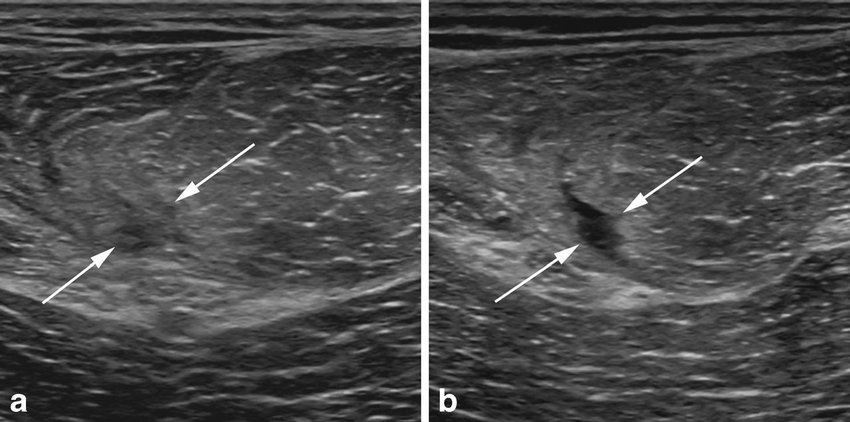

لتشخيص التمزقات العضلية 👨🏽‍⚕️📝📸

الفحص السريري Physical examination

الرنين المغناطيسي MRI

اشعة الموجات الفوق صوتية Ultrasound